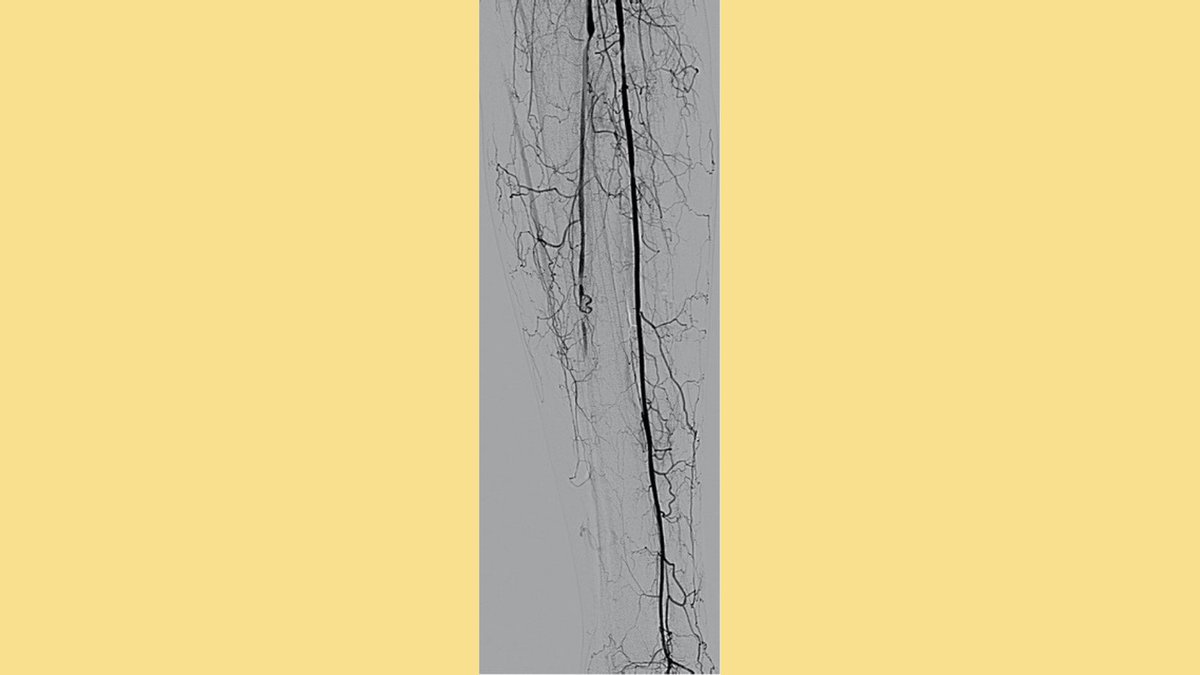

Option Elite filter in since February 2021 initially failed loop snare and forceps techniques, taken out with @PhilipsHealth #CavaClear laser sheath. 9 seconds of laser time. Great experience! #filterout @IrColorado @pj_rochon